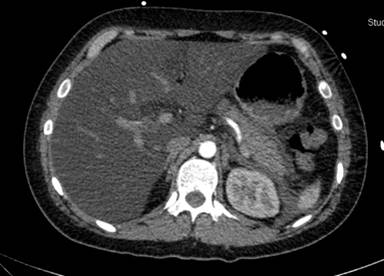

A twenty-two-year old male with no past medical history, presented with mid abdominal pain radiating to the chest with shortness of breath. Patient was sent to the emergency room for a chest computed tomography (CT) scan after a routine laboratory test at an urgent care center showed elevated D-dimer levels. Patient denied any fever, chills, recent travel or prior history of thromboembolic disease. Patient was adopted and does not know his family history. His blood pressure was 139/74 mmHg, heart rate 67 beats/minute; respiratory rate 18 cycles/minute, oxygen saturation was 98% on room air. Clinical examination showed mild epigastric tenderness, otherwise unremarkable. His chest CT scan was negative for pulmonary embolism but showed some stranding at the tail of the pancreas suspicious for acute pancreatitis (Figure 1). Routine laboratory tests showed white blood cell count of 14.4/µL, elevated lipase (754 U/L), creatinine (0.79 mg/dL), ESR (1 mm/h), C-reactive protein (0.08 mg/dL), alanine aminotransferase (23 U/L), aspartate aminotransferase(71 units/L), alkaline phosphatase (139 units/L), gamma-glutamyltransferase (209 U/L; reference range: 1-54 U/L). Patient was kept nil per oral, intravenous normal saline and pain medications were commenced. Patient admitted to drinking some whiskey daily. A right upper quadrant ultrasound did not show any evidence of gallstones but revealed a fatty liver. His lipid panel and triglycerides were normal. A urine toxicology screen was positive for cocaine and marijuana. His ethanol blood level was normal.

Figure 1. Abdominal view of CTA of the chest showing stranding adjacent to the body and tail of the pancreas with associated fluid suggestive of acute pancreatitis. |